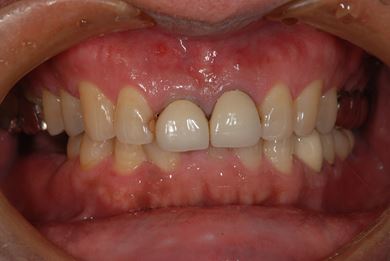

インプラントの症例写真 IMPLANT

インプラント治療

| 性別/年齢 | 男性 / 59歳 | ||||||||||||||||||||||||||||||||

| 主訴 | インプラント治療を検討中。 | ||||||||||||||||||||||||||||||||

| 治療方針 | 欠損部分インプラント治療により、機能的・審美的回復を行う。 | ||||||||||||||||||||||||||||||||

| 治療内容 | インプラント2本、ハイブリッドセラミック2本 | ||||||||||||||||||||||||||||||||

| 総治療費 | 738,675円 | ||||||||||||||||||||||||||||||||

| 治療期間 | 8ヶ月 |